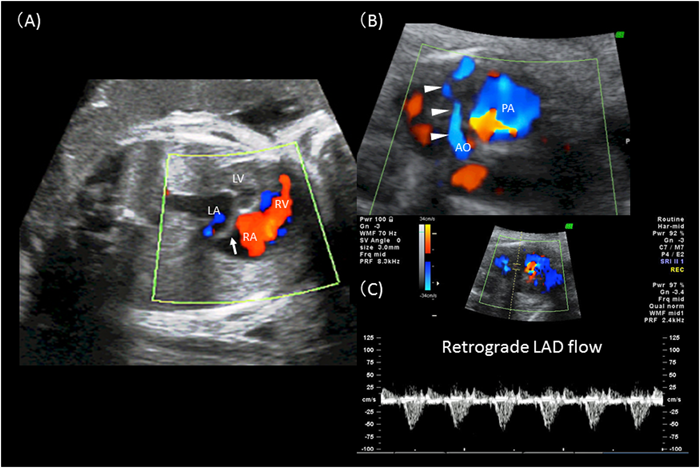

1886年にBrooksにより本疾患の最初の剖検報告が行われた53).その後1933年にBland, WhiteおよびGarlandらにより本疾患の系統だった報告が最初になされたことから,彼らの頭文字をとってBWG症候群とも呼ばれる54).本疾患の頻度は1/30万生産児と稀であり,また特殊な病態では学童期や成人期に発見される(成人型)こともあるが,ほとんどの症例は生後2~3カ月で発症する(乳児型)55).初発症状が重度の循環不全によるショックのことが多くあり,大動脈弁狭窄や大動脈縮窄等を除外した上で拡張型心筋症との鑑別が重要になる.心エコーによる左冠動脈血流の描出が非常に重要になるが,左冠動脈の肺動脈還流部は症例によっては確認困難なことがある.しかし,末梢左冠動脈は比較的容易に描出でき,カラードプラのスケールを下げることにより冠動脈内の血流を確認し,拡張期もしくは連続性の逆行性血流を確認できるようであれば診断は確定的となる(Fig. 6).左冠動脈還流領域の虚血性変化,特に左前乳頭筋のエコー輝度上昇や前中隔から左室前壁の心内膜エコー輝度上昇なども支持所見として有用である.また,心拡大と乳頭筋機能不全に伴った重度の僧帽弁閉鎖不全を合併する(Fig. 6).右冠動脈の拡大も支持所見として有用であるとされるが,この所見は側副血管の発達が未熟な乳児期早期には顕著でないことが多い.左冠動脈の肺動脈への開口部は肺動脈背側(facing sinus)が多いが,前肺動脈洞や左右肺動脈分岐部等の大動脈基部から離れた場所へ還流する場合もあり,還流部位の診断は手術法の選択の上で術前情報として必要である56).エコーでの診断が不可能な場合には造影検査を行う.なお,成人型おいては,左冠動脈の肺動脈還流部に狭窄が存在し,肺動脈へのcoronary stealが起こりにくい血行動態に加えて,右冠動脈から左冠動脈灌流領域への側副血行路が非常に発達していることが多い.また,ほとんどのALCAPA症例は単独の心疾患であることが多いが,動脈管開存症等の短絡性心疾患を合併することにより肺高血圧が維持されている場合や末梢性肺動脈狭窄により主肺動脈圧が高圧に維持されている場合などもcoronary stealを軽減し症状が緩和されていることがある.これらの症例では合併心奇形の治療後に急速に心筋虚血が進行しALCAPAの症状が出現することがある.治療については,乳児型においては診断が確定次第,全例速やかに手術介入を行う必要がある.一方,成人型においても突然死の発生率が8割を越えることから,たとえ無症状で虚血所見を欠く症例に対しても手術介入を行うことが推奨されている2).手術には左冠動脈の大動脈への移植やTakeuchi法等が知られているが,詳細については他章に譲る.なお,合併する僧帽弁閉鎖不全に対して僧帽弁の形成術を同時に行うかどうかについては未だ統一された見解はない.

Pediatric Cardiology and Cardiac Surgery 32(2): 95-113 (2016)

Fig. 6 Anomalous left coronary artery from the pulmonary artery (ALCAPA)

(A): Left coronary artery: Note the retrograde flow in the left coronary artery (white arrowheads) that drains into the posterior aspect of the pulmonary artery.(B): Right coronary artery at the normal position of the right aortic sinus with antegrade flow.(C): Short axis view of the left ventricle: Note the increased brightness of the endocardium of the anteroseptum and anterolateral papillary muscle (arrow).(D): Apical chamber view displays moderate mitral regurgitation.AO: aorta; LCA: left coronary artery; PA: pulmonary artery; RCA: right coronary artery.